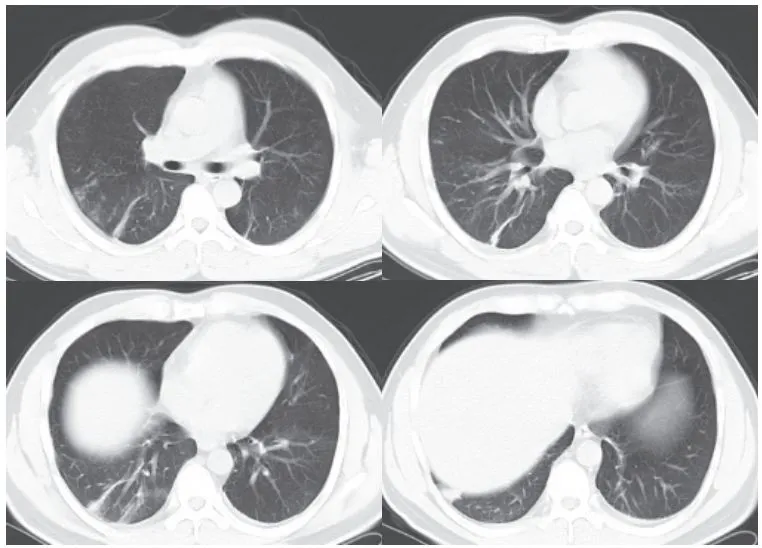

(二)腺病毒性肺炎

腺病毒属于哺乳动物腺病毒属,为无包膜的双链 DNA 病毒。腺病毒性肺炎易发生于婴幼儿或免疫功能障碍的人群。本病起病急,高热,并发症多

影像学表现:

(1)多呈大叶性分布(图 3-2A),实质、间质均受累

(2)可有空气潴留征、马赛克样灌注及肺气肿

(3)显示类似细菌性肺炎的支气管肺炎征象(肺叶或节段性分布),如腺泡结节、 GGO、实变等(图 3-2B)

(4)后遗症:闭塞性细支气管炎、支气管扩张、肺纤维化、单侧透明肺等